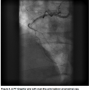

When he came to our hospital for a second opinion, a repeat catheterization showed a mid RCA in-stent chronic total occlusion (CTO) (Figure 1). The left system was free of any significant disease and septal collaterals filled the distal posterior descending artery (Figure 2). The left ventriculography revealed preserved systolic function with normal inferior wall motion.